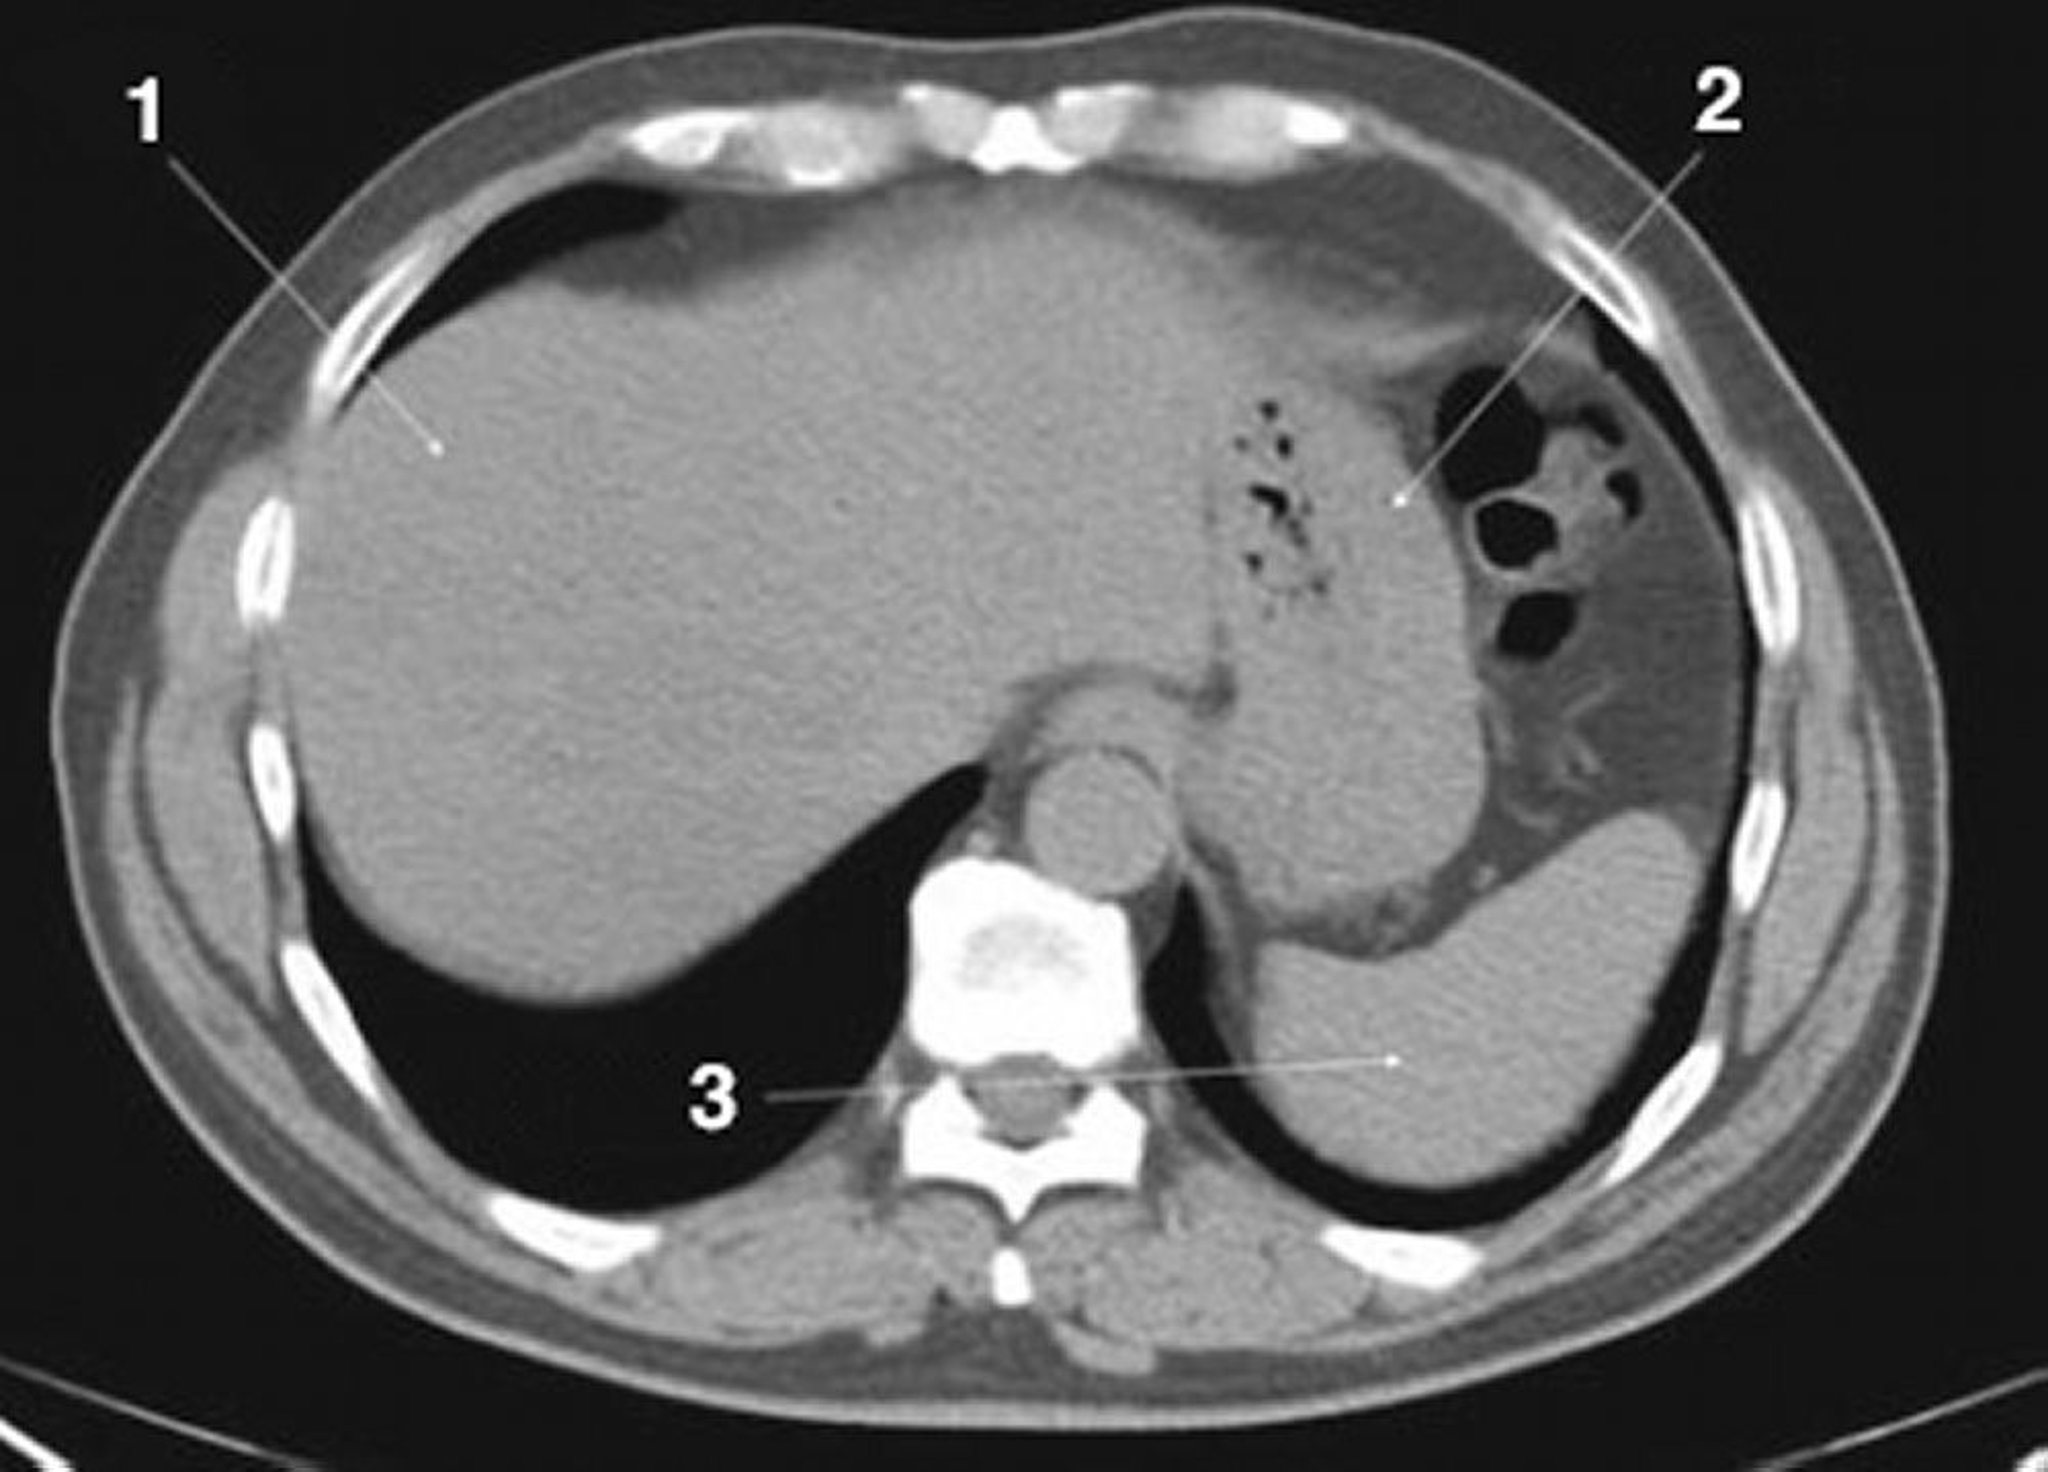

TDM sans contraste de l'abdomen et du bassin montrant une anatomie normale (diapositive 3)

1 = foie; 2 = estomac; 3 = rate.